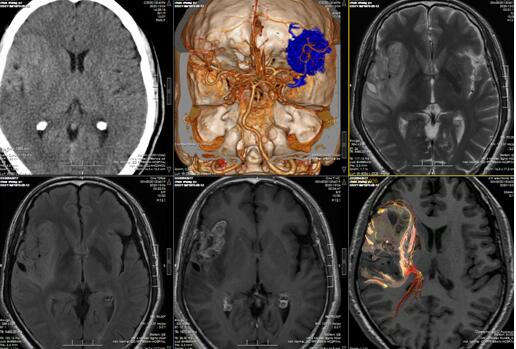

检查:患者入院后查体:神志清楚,对答切题,双侧瞳孔等大等圆直径2.5mm,对光反射灵敏,四肢肌力5级,肌张力正常,生理反射存在,病理反射未引出。我院 3.0TMR颅脑平扫, MR弥散成像全套(DWI)检查意见: .右侧额颞岛叶-放射冠占位性病变,结合MRS,考虑高级别胶质瘤,胶质母细胞瘤或间变性星形细胞瘤可能性大;病灶包绕右侧大脑中动脉主干及分支,邻近柔脑膜存在脑膜转移可能;2.弥漫性轻度脑萎缩。

图一、术前影像显示;MRI明显强化